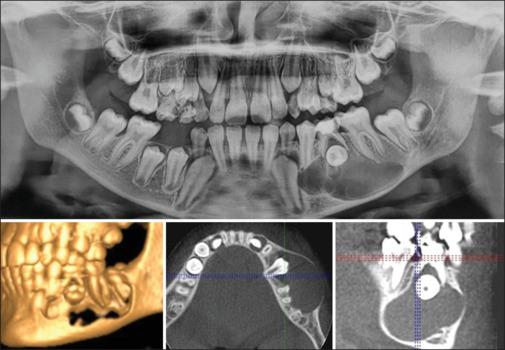

根性囊肿是颌面部最常见的炎性囊肿之一,起源于赫氏上皮根鞘的残余。这些通常被诊断为x线片上的偶然发现,很少有症状并且进展缓慢。减压可以作为一种保守治疗方法用于治疗儿童大根性囊肿,以获得满意的愈合和对邻近重要结构的最小损害,同时允许继发牙齿的爆发。本文讨论了一名12岁儿童的大根状囊肿的治疗方法,该囊肿引起下颌管移位和牙胚发育,通过减压导致骨愈合和移位的连续前磨牙自发爆发,并定期随访40个月。虽然减压是一种众所周知的方法,但本病例的长期随访强调了小儿神经根囊肿病例自然愈合的潜力,使解剖恢复正常,没有任何功能损害。本文还强调了定期临床和影像学随访对牙髓治疗的非生命乳牙的重要性。

Radicular cysts are one of the most common cysts of inflammatory origin involving the maxillofacial region that arise from the remnants of Herwig's epithelial root sheath. These are often diagnosed as incidental findings on radiographs, which are seldom symptomatic and are slowly progressive. Decompression could be used as a conservative treatment approach for the management of large radicular cysts in children to have satisfactory healing and minimum damage to adjacent vital structures, simultaneously allowing the eruption of succedaneous tooth. This paper discusses the management of a large radicular cyst in a 12 year old, causing displacement of the mandibular canal and developing tooth germ using decompression that resulted in bony healing and spontaneous eruption of displaced succedaneous premolar, with a periodic follow-up for 40 months. Although decompression is a well-known approach, the present case with long-term follow-up emphasizes the potential of spontaneous healing in pediatric radicular cyst cases restoring the anatomy to normal without any functional impairment. This paper also highlights the importance of periodic clinical and radiographic follow-up in pulpally treated nonvital primary teeth.